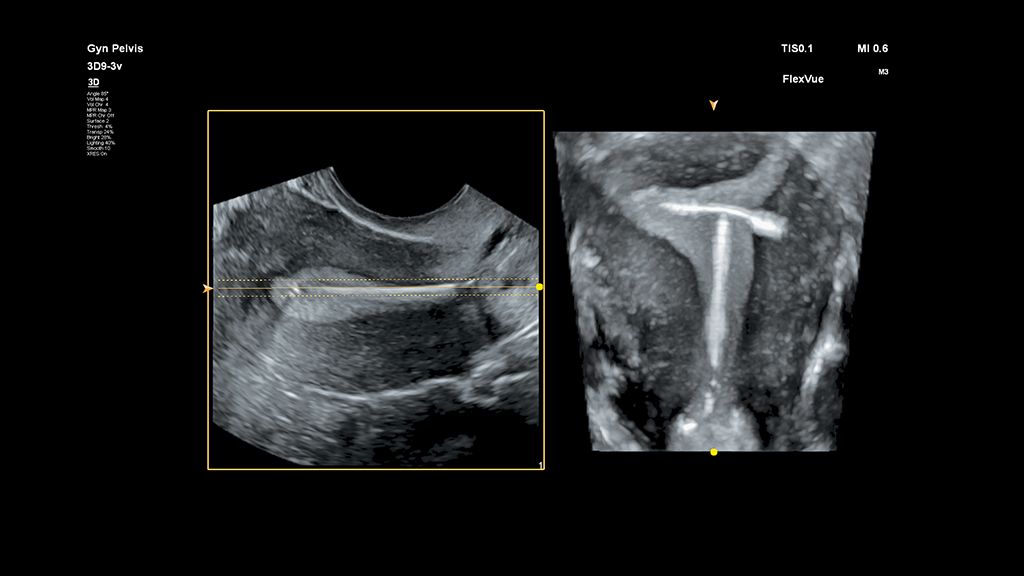

Demonstrated results using FlexVue

It (FlexVue) takes all of the complications out of MPR and manipulation of a surface-rendered volume. By deploying a straight line or a curved trace or continuous trace, we can take a curved image, flatten it out and make it a single planar image.